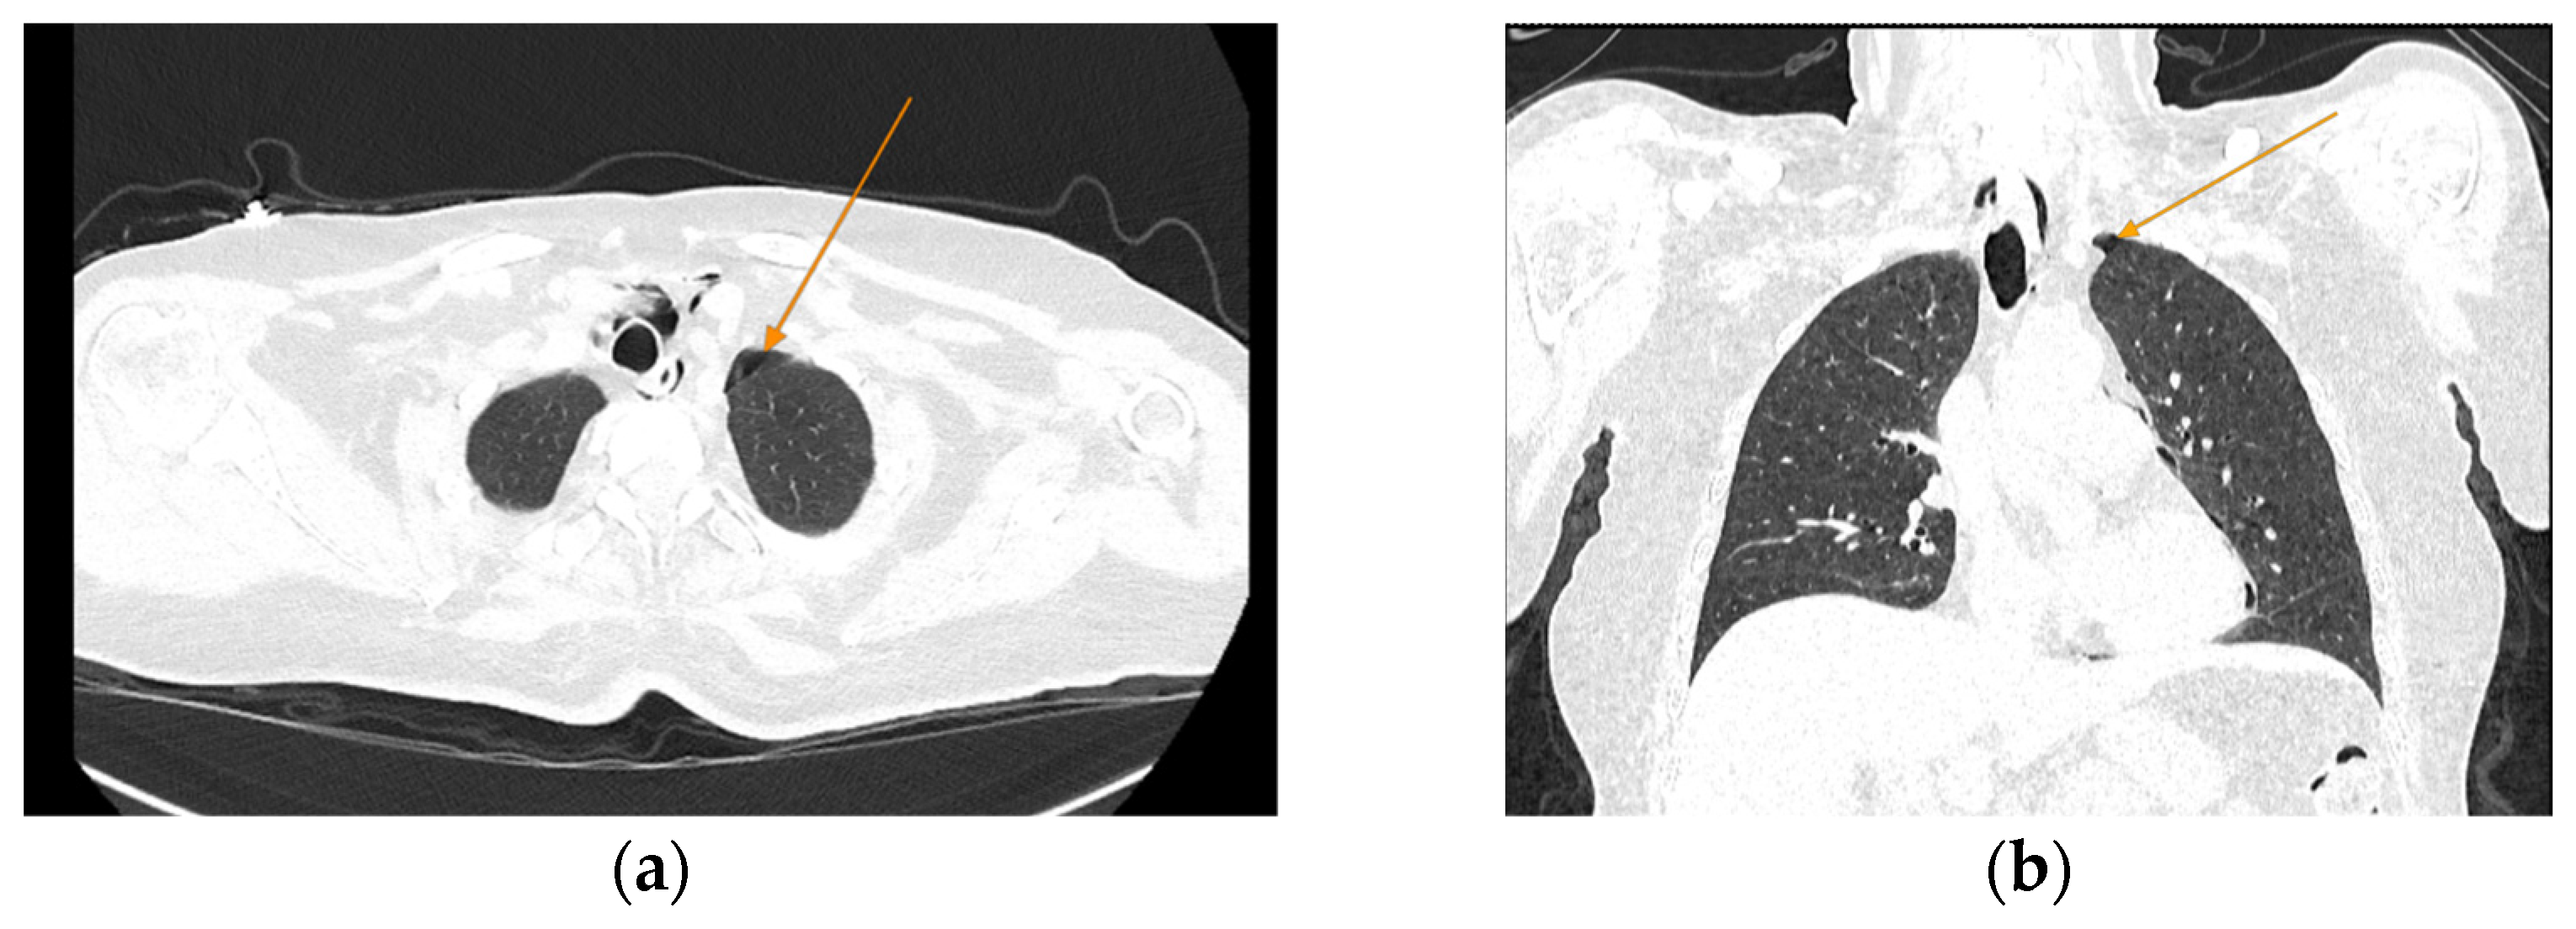

The patient was referred to diabetology in order to be admitted to hospital. Although the patient presented a good clinical and biological evolution, her condition deteriorated after about 12 h; therefore, another chest CT scan was performed, revealing extension of the pneumomediastinum in comparison to the prior scan and the presence of an additional left pneumothorax measuring approximately 7 mm (Figure 5).

Figure 5.

Chest CT showing the presence of pneumothorax (arrows): (a) axial view; (b) coronal view.